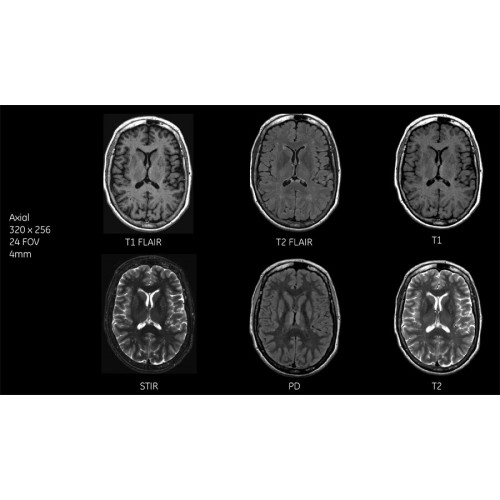

Диагностические возможности аппарата

Многофункциональность исследований

МРТ аппарат GE SIGNA Voyager 1.5T позволяет проводить полный спектр магнитно-резонансных исследований, включая нейровизуализацию, исследования опорно-двигательного аппарата, органов брюшной полости и малого таза, а также специализированные кардиологические программы.

Поддержка современных протоколов

Аппарат поддерживает все актуальные диагностические протоколы и совместим с современными медицинскими информационными системами, обеспечивая интеграцию в цифровую инфраструктуру клиники.